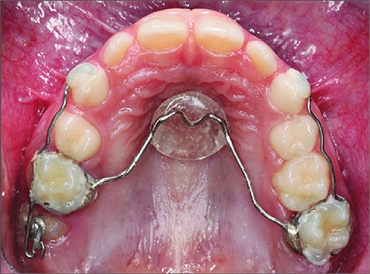

There are various modifications of this appliance. When a crib like arrangement is fused to the acrylic button, it is used for correcting the thumb-sucking habit. Another modification involves an arrangement which is done to restrict the permanent molar only on one side. Next, there is a modification where the molars are pushed back if at all they have moved forward towards the missing space. This type of appliance is active in nature.